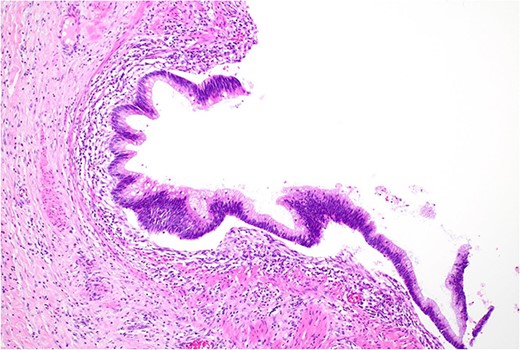

Histopathology macroscopically identified a 42-mm cystic caecal mass adjacent to the ileocaecal valve (Figs 4–5). Microscopic examination revealed a duplication cyst involving the ileal and colonic tissue comprised of a complete duplication of the colonic wall including mucosa, submucosa and muscularis propria, which was shared with the involved colon (Fig. 6). There was no mucosal connection to adjacent normal bowel. There was some ulceration with inflammatory changes in the overlying mucosa suggestive of prior cyst perforation and areas of attenuated villiform mucinous epithelium with features of low grade dysplasia (Figs 7-8). Special stains for organisms (Periodic Acid-Schiff (PAS), Fredericamycin A (FMA), Ziehl-Neelsen (ZN) and modified ZN) were negative. There were no granulomas, heterotopic mucosa or evidence of malignancy. Twenty-nine lymph nodes were identified with no evidence of malignancy.

Remnant of normal colonic epithelium (left) within the duplication cyst that shares common muscularis propria with the terminal ileum (right), low power.

Area of dysplastic mucosa (right) within the duplication cyst that shares a common wall with the right colon (left), low power.